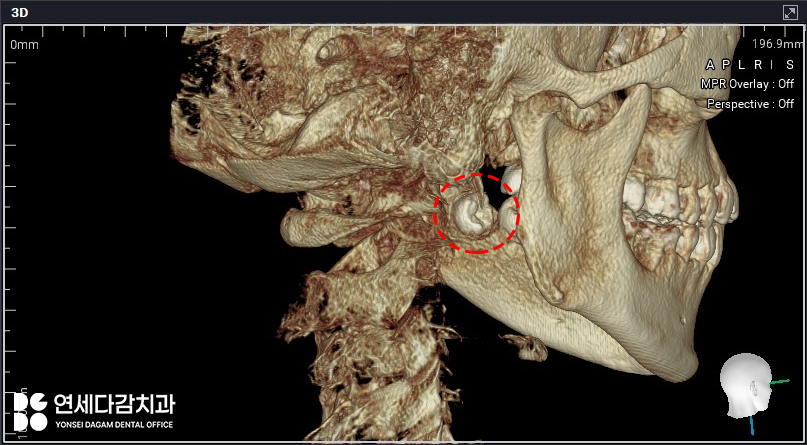

간혹 치아의 머리 부분인 치관이

설측(혀 쪽)으로 향하고 있는

경우가 있습니다.

이런 상황에서는 발치 과정이

훨씬 까다로워집니다.

오금동 치과 에서 이렇게 말씀드린 이유는

해부학적 구조 때문입니다.

설측에는 혀신경과

큰 혈관 같은 중요한

해부학적 구조물들이 위치하고 있어

이를 빼는 과정에서

특별히 세심한 주의가 필요합니다.

따라서 절개부터 발치까지

모든 과정이 더욱 섬세하게

이루어져야 됩니다.

이러한 복잡한 케이스에서는

CT 촬영을 통해 3차원적인

구조 분석을 통해

안전한 발치 전략을

미리 수립하는 것이

필수 과정입니다.